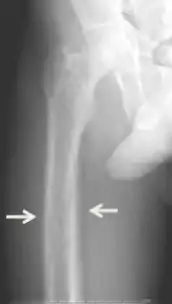

Renal osteodystrophy is usually diagnosed after treatment for end-stage kidney disease begins; however the CKD-MBD starts early in the course of CKD.[1][6] In advanced stages, blood tests will indicate decreased calcium and calcitriol (vitamin D) and increased phosphate, and parathyroid hormone levels. In earlier stages, serum calcium, phosphate levels are normal at the expense of high parathyroid hormone and fibroblast growth factor-23 levels. X-rays will also show bone features of renal osteodystrophy (subperiostic bone resorption, chondrocalcinosis at the knees and pubic symphysis, osteopenia and bone fractures) but may be difficult to differentiate from other conditions. Since the diagnosis of these bone abnormalities cannot be obtained correctly by current clinical, biochemical, and imaging methods (including measurement of bone-mineral density), bone biopsy has been, and still remains, the gold standard analysis for assessing the exact type of renal osteodystrophy.[6][15]

Brown tumors in the pelvis and a hip fracture.[17]